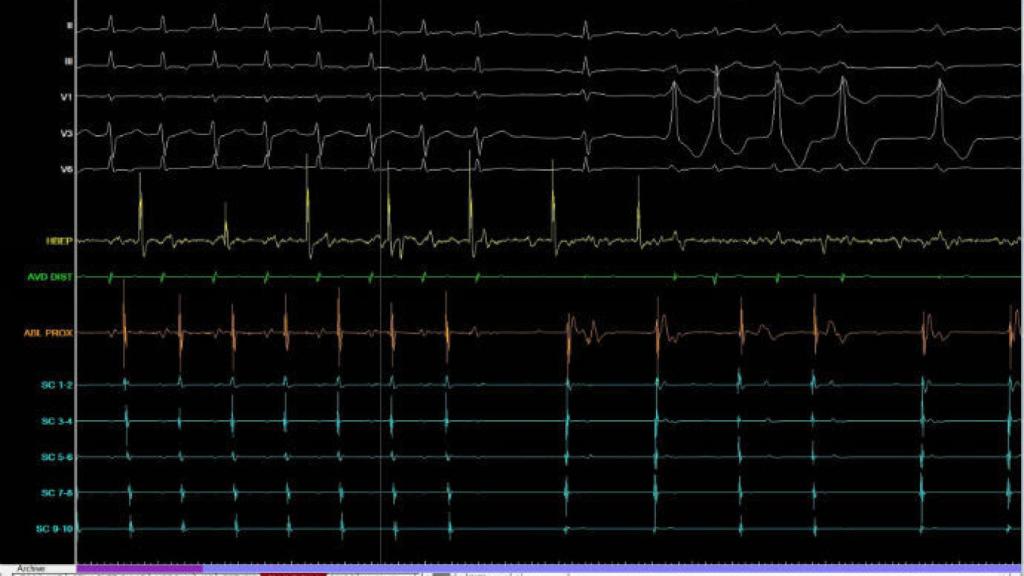

El grupo de investigación de Ingeniería Electrónica, Biomédica y de Telecomunicaciones de la Universidad de Castilla-La Mancha (UCLM), junto a investigadores de la Universidad Politécnica de Valencia (UPV), han desarrollado un nuevo software que mejora la caracterización de arritmias cardiacas al poder ofrecer al cardiólogo información "desconocida hasta el momento" sobre estas alteraciones.

Este estudio, que ha sido publicado en la revista científica 'Annals of Biomedical Engineering', explica que su incorporación a los equipos clínicos de electrofisiología cardiaca actuales permitiría obtener una señal "más nítida, definida y sin distorsiones en todo tipo de arritmias", fundamentalmente la fibrilación auricular, la más común en la actualidad, según ha informado la UCLM en una nota de prensa.

En este trabajo, los investigadores realizaron un estudio en el que demostraron cómo los sistemas actuales de electrofisiología cardiaca realizan un tratamiento de la señal que puede alterar sustancialmente la morfología de los registros obtenidos.

"El problema reside en que las técnicas de filtrado que utilizan pueden ser inadecuadas, por lo que, si dichos registros son empleados posteriormente como base para la caracterización electrofisiológica del paciente, puede producir errores significativos en la estimación de parámetros esenciales sobre su estado arrítmico", explica Rieta.

El software desarrollado por los investigadores de UCLM y de la UPV evita esos errores. De hecho, permite reducir hasta en un 40 por ciento la distorsión introducida por los sistemas convencionales de adquisición electrofisiológica.